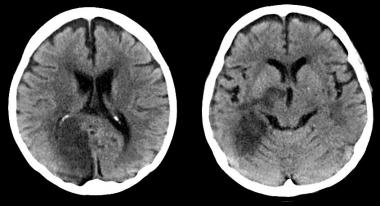

En 30 años de seguimiento de una cohorte británica, el consumo de 2 a 3 bebidas alcohólicas por día se asoció con lesiones en la resonancia magnética cerebral y peores resultados en las pruebas de lenguaje. BMJ, 6 de junio de 2017